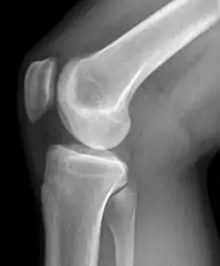

يُطلق اسم مفصل الركبة عند الفقاريات، على المفصل المركزي للأطراف الخلفية، أما عند الإنسان فيُطلق على المفصل المركزي للأطراف السفلية.[1] فالركبة هي مفصل يربط الفخذ مع الساق، وهي أكبر مفصل في الجسم البشري.[2] يتكوّن مفصل الركبة من مفصلين اثنين: مفصل بين عظم الفخذ والساق، ومفصل بين عظم الفخذ والرضفة.[3] وتغطي الغضاريف الناعمة أسطح هذه العظام المكونة للمفصل حتى يضمن ذلك سهولة في الحركة. ويوجد بين عظمتي الفخذ والقصبة غضاريف هلالية تعملان كوسادتين تساعدان على امتصاص الصدمات أثناء المشي والجري. تعد الركبة مَفْصِلٌ رَزِّيٌّ لَولَبِيّ متحرك (مشترك اللقمة المحورية)[4] يسمح بالثني والبسط وكذلك الدوران الطفيف الداخلي والخارجي. يعتبر مفصل الركبة عُرضة للإصابة سواء الإصابة الحادة أو حدوث هشاشة العظام.

![]() الركبة اليمنى ، نظرة جانبية من الخارج (وحشية). الركبة اليمنى ، نظرة جانبية من الخارج (وحشية). | |